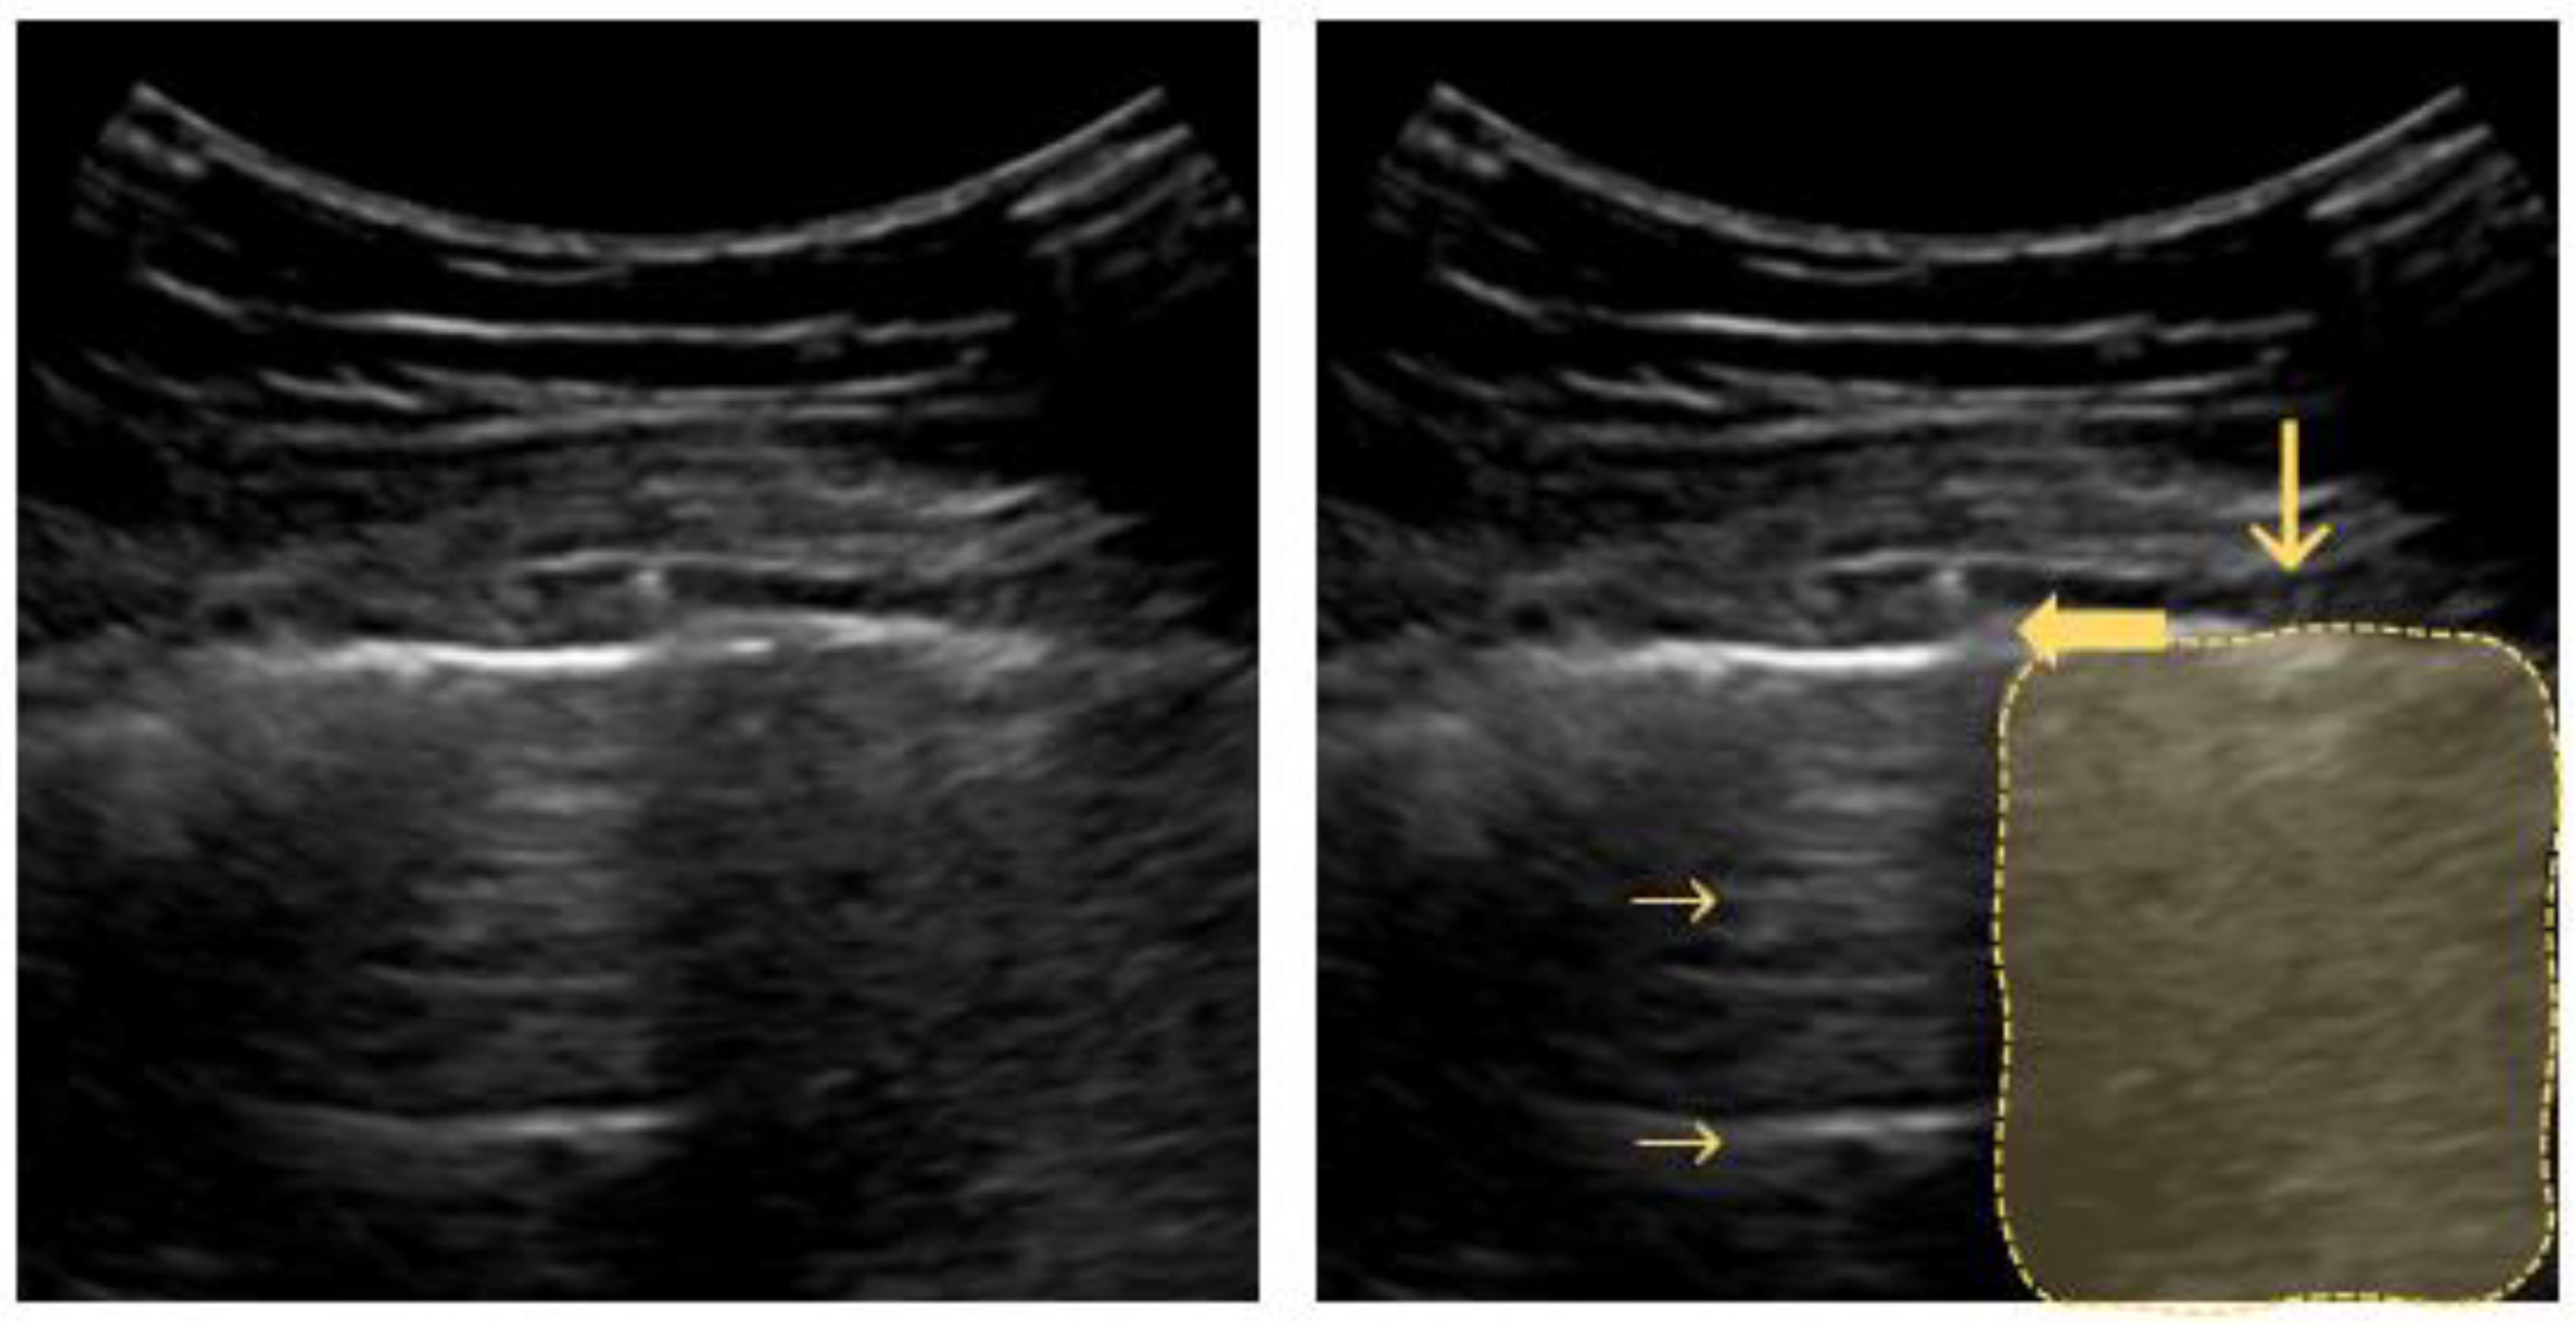

4.3. Lung Consolidation